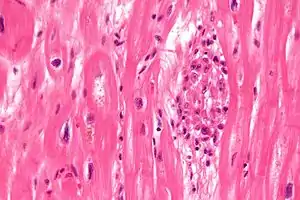

| Aschoff bodies are microscopic structures seen in patient with rheumatic fever | |

Microscopically, Aschoff bodies are areas of inflammation of the connective tissue of the heart, or focal interstitial inflammation. Fully developed Aschoff bodies are granulomatous structures consisting of fibrinoid change, lymphocytic infiltration, occasional plasma cells, and characteristically abnormal macrophages surrounding necrotic centres. Some of these macrophages may fuse to form multinucleated giant cells. Others may become Anitschkow cells or "caterpillar cells," so named because of the appearance of their chromatin.

The Aschoff nodules are foci of T lymphocytes, occasional plasma cells, and activated macrophages (Anitschkow cells) pathognomonic of rheumatic fever. These macrophages have abundant cytoplasm and central round nuclei in which chromatin condenses into a central, slender, wavy ribbon, the reason why they are sometimes called "caterpillar cells". They are especially found in the vicinity of small blood vessels in the myocardium and endocardium and occasionally in the pericardium, and also the adventitia of the proximal part of the aorta. Lesions similar to the Aschoff nodules may also be found in extra-cardiac tissues.